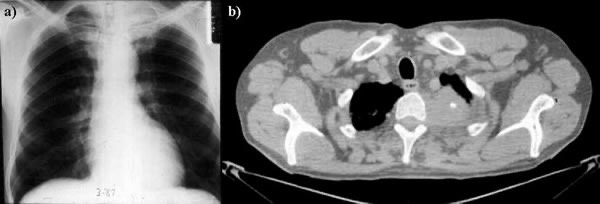

1425. Учитывая локализацию патологического образования в грудной клетке по данным томографического среза и рентгенографии органов грудной клетки

для удаления опухоли целесообразно использование